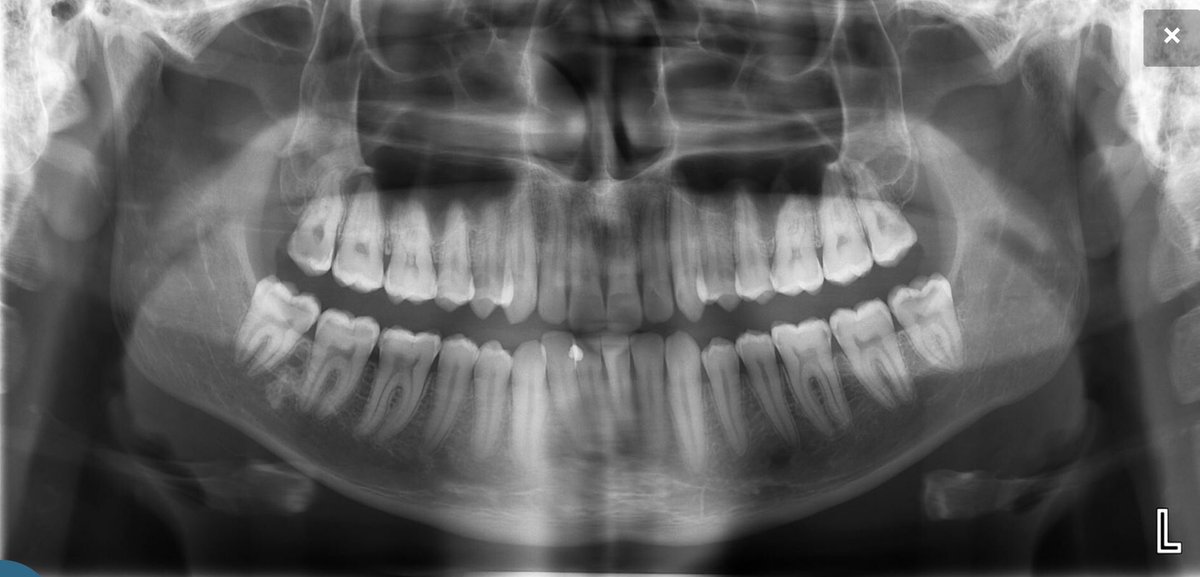

النوع الثالث:وهوالاشعة البانورامية وتسمى أيضا Orthopantomogram (OPG)

وهي الاشعة التي تدور حول رأس المريض لتعطي صورة شاملة للاسنان والأنسجةالمحيطةوالجيوب الأنفية ومفصل الفك والفكين واستخداماتها منها:

وأشعة البانوراما 👇 تطورت اجهزتها مع مرور الزمن لكن مازالت لاتعادل الاشعة الصغيره PA لذلك لا تستخدم بشكل روتيني ويومي وإنما للحاجه كما ذكرنا سابقاً

وعند عمل اشعة البانوراما اوالأشعة المقطعية ثلاثية الأبعاد يجب اتباع التعليمات بشكل دقيق من حيث عدم الحركة واتجاه الرأس

وان لايكون هناك عائق او وجود جسم غريب "كحلق الإذن" قد يؤدي الى التسبب بتشويه الصوره والتسبب بإعادة الأشعة مرة اخرى